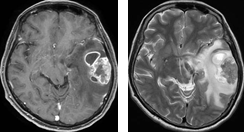

症例 1

肺癌による左側頭葉転移性脳腫瘍に対してEGFR変異陽性の結果を踏まえて イレッサ(ゲファチニブ)の単独投与のみで治療したところ、腫瘍が著明に縮小しました。その後再発なく経過しています。